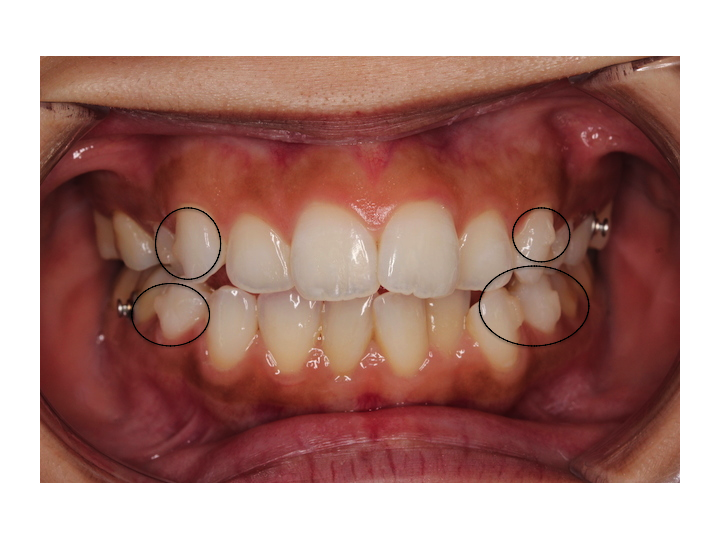

さらに今日からアタッチメントという突起が右上下と左上下につきました。

厚さ1mm程度の白いレジン素材で出来ており、歯の外側につきます。

歯の表面に凹凸を増やすことで歯の動きをより正確にするんだそうです。

(アタッチメントがついた歯に印をつけてみました。膨らんでいるのがアタッチメントです。)